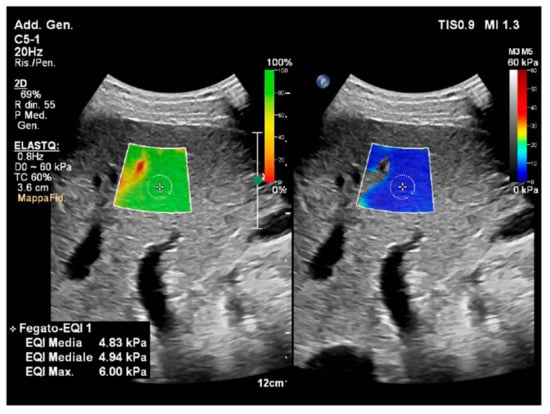

4.1. Liver